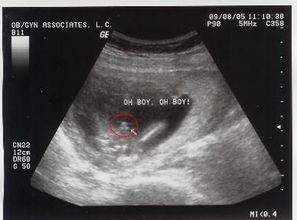

20周胎儿系统B超检查,又称为大排畸检查,是孕期中的一项重要检查。这一阶段的胎儿已经发育到一定程度,器官结构基本形成,通过B超检查可以全面了解胎儿的生长发育情况,及时发现并排除严重的胎儿畸形。

一般来说,20周胎儿系统B超检查的最佳时间为妊娠20-24周。此时,胎儿各器官已经发育成熟,羊水量适中,胎儿相对容易变换体位,有利于超声筛查胎儿结构。